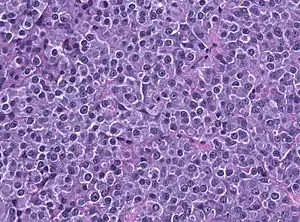

-

Invasive prolactinoma showing invasion into the left temporal lobe -

Prolactinoma on MRI